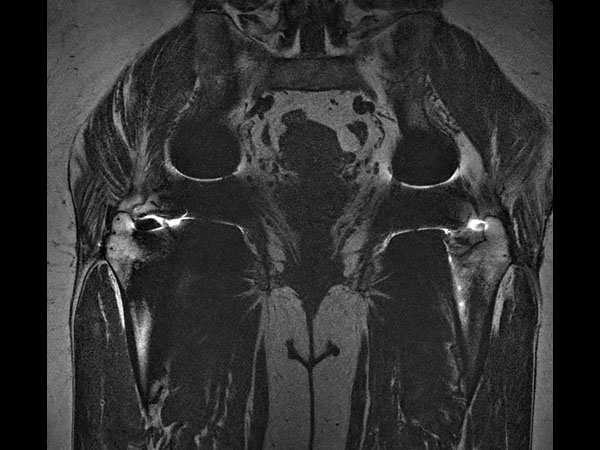

Coronal T1w TSE